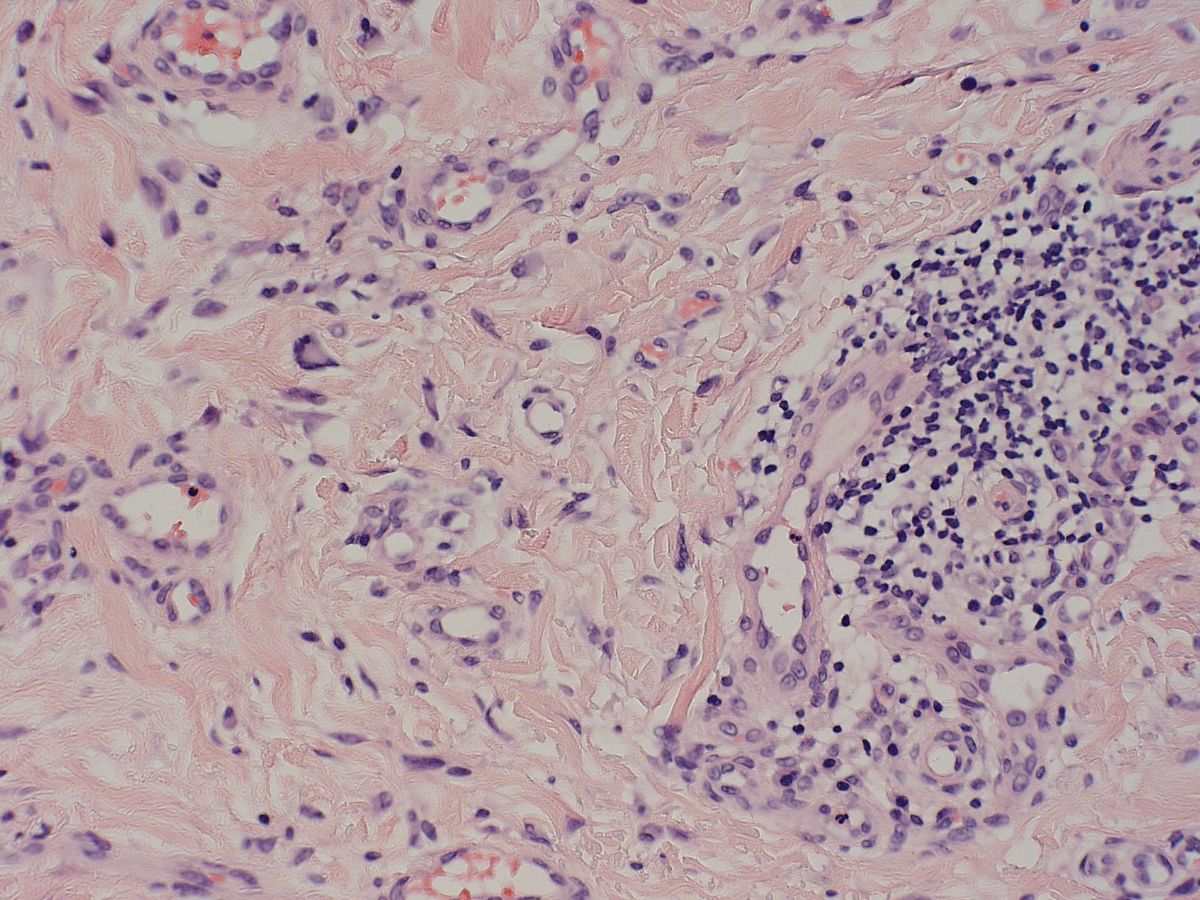

PA:Epidermis licht acanthotisch verbreed, in de

dermis een diffuse en multicentrische toename van capillaire vaatstructuren.

Het endotheel is nadrukkelijk aanwezig, perivasculair bevindt zich een rondkernig

ontstekingsinfiltraat. Ook worden meerkernige reuscellen gezien.